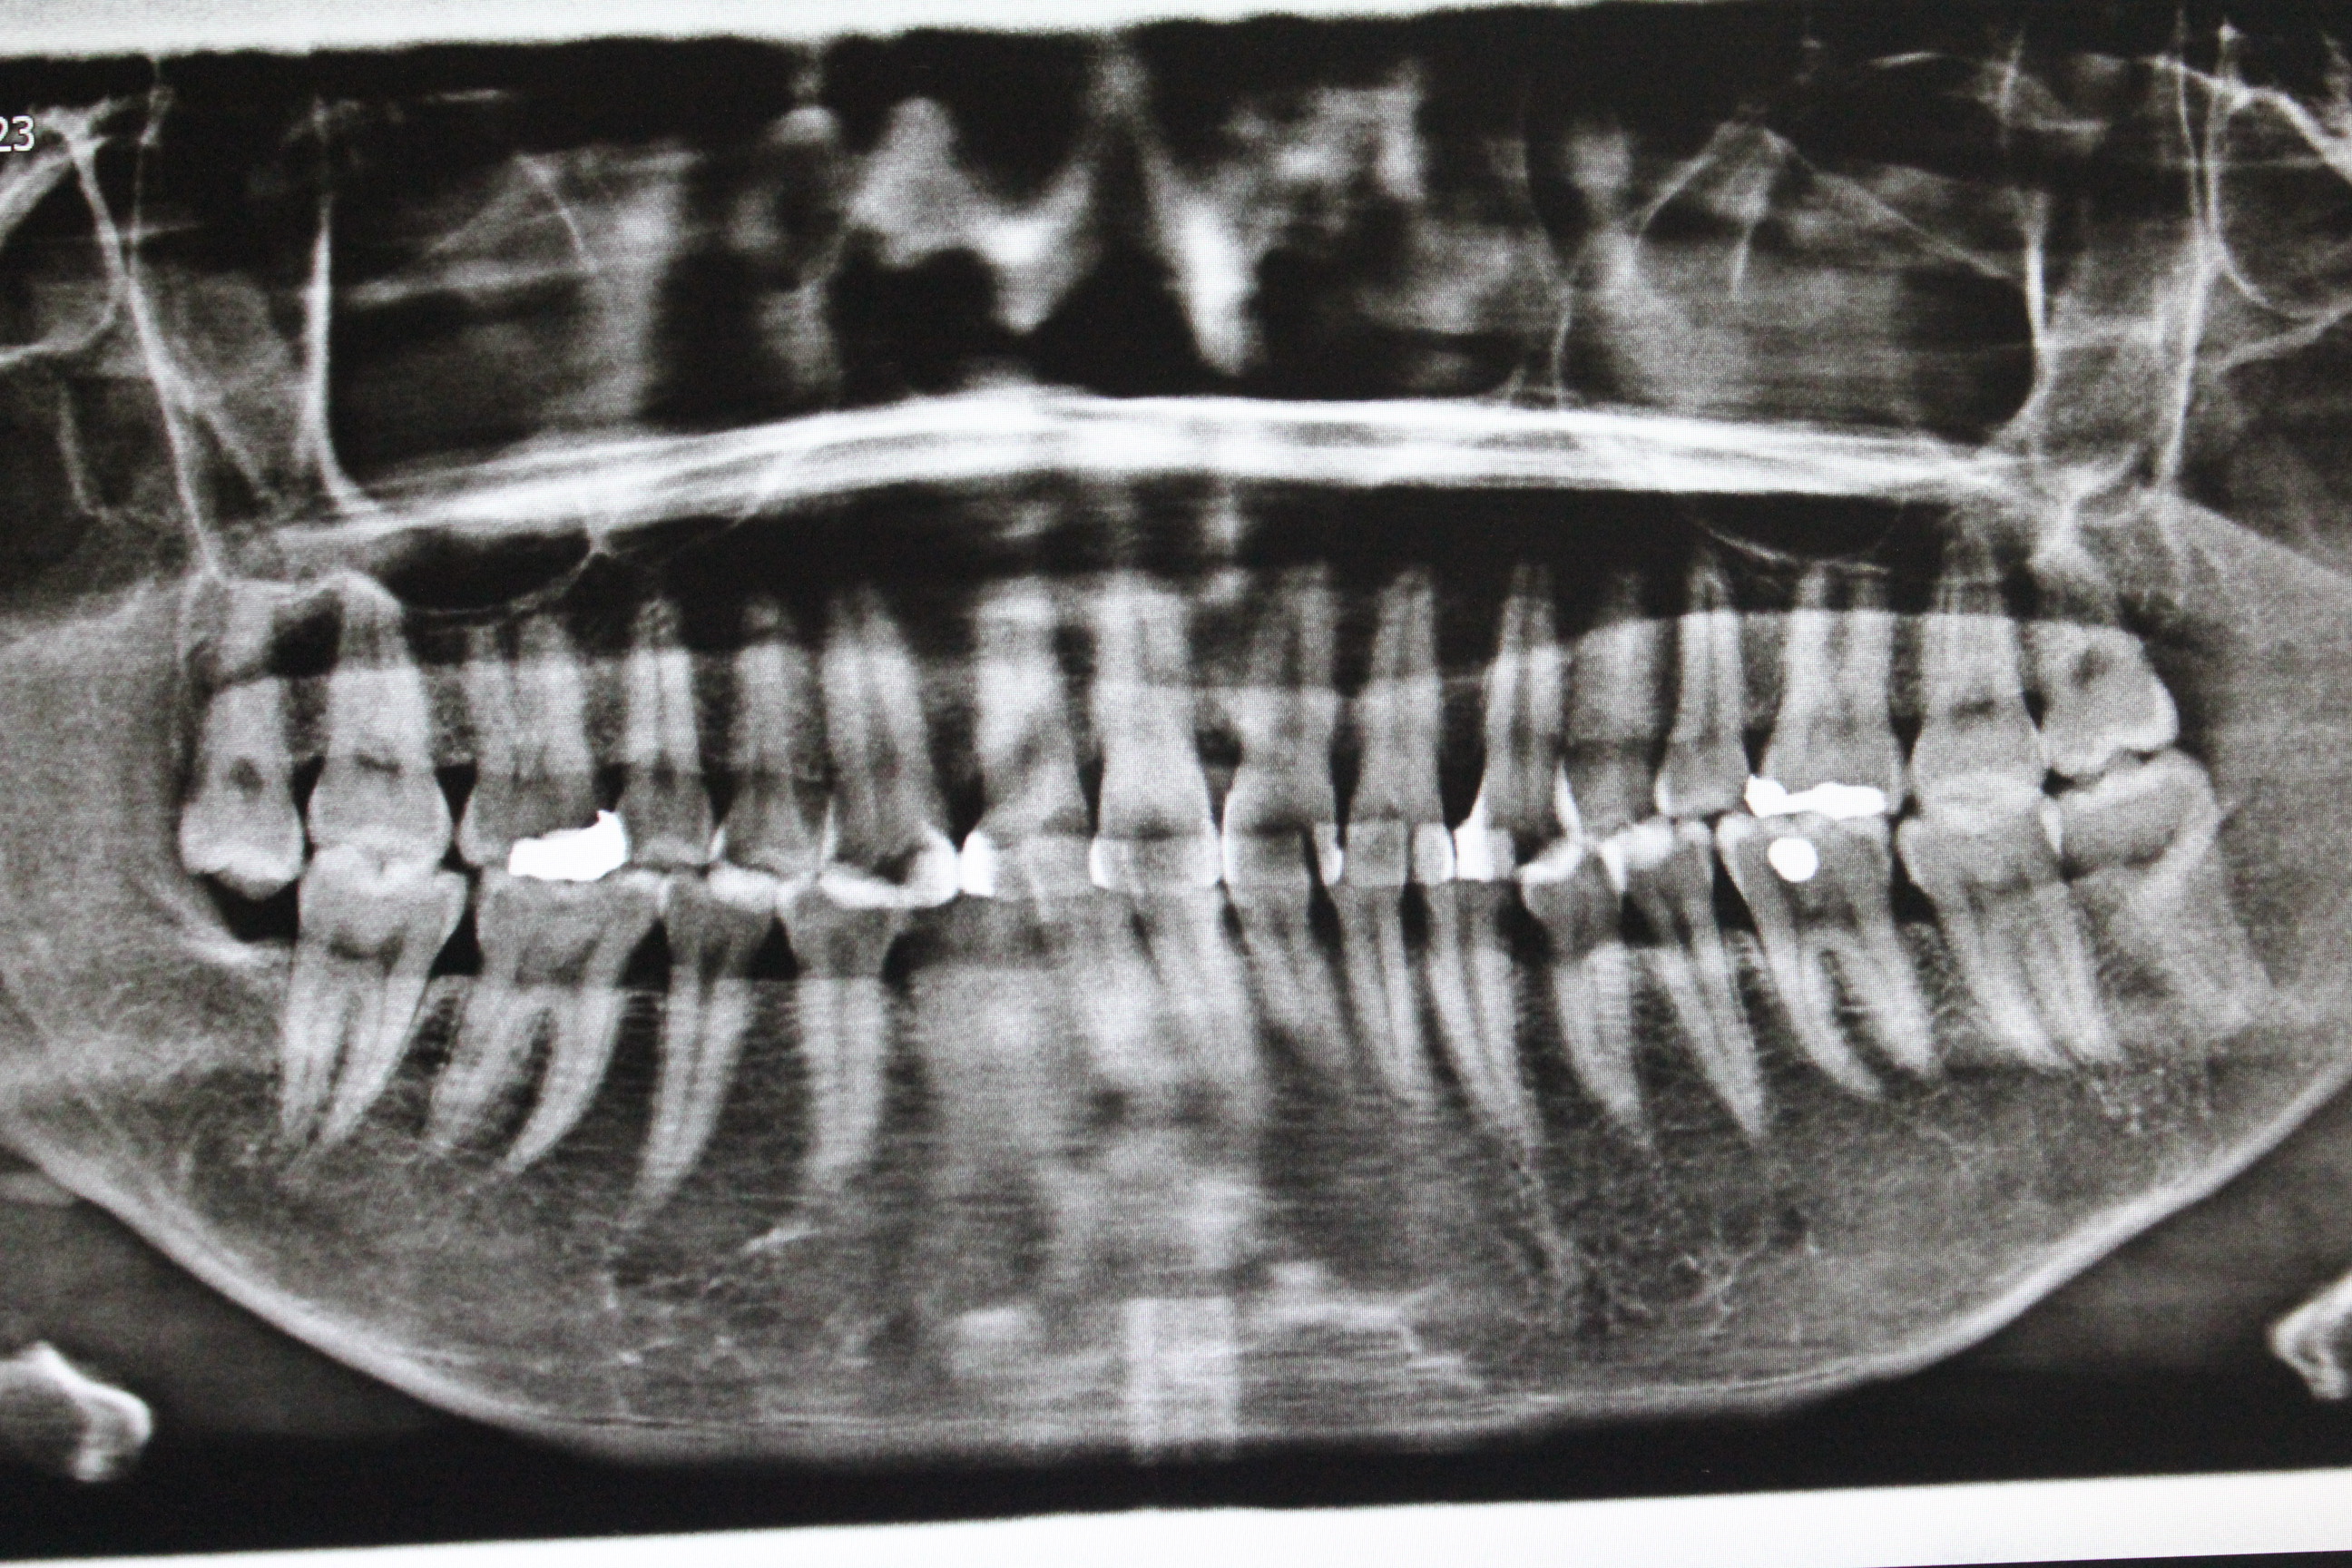

수술전 - 파노라마 엑스레이